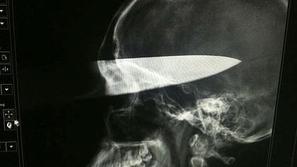

Sreča v nesreči Nož v glavo, vendar preživel Med pretepom mu je napadalec zabodel 30-centimetrski nož v obraz. Neverjetna sreča: nož zgrešil vse vitalne dele, mlade…